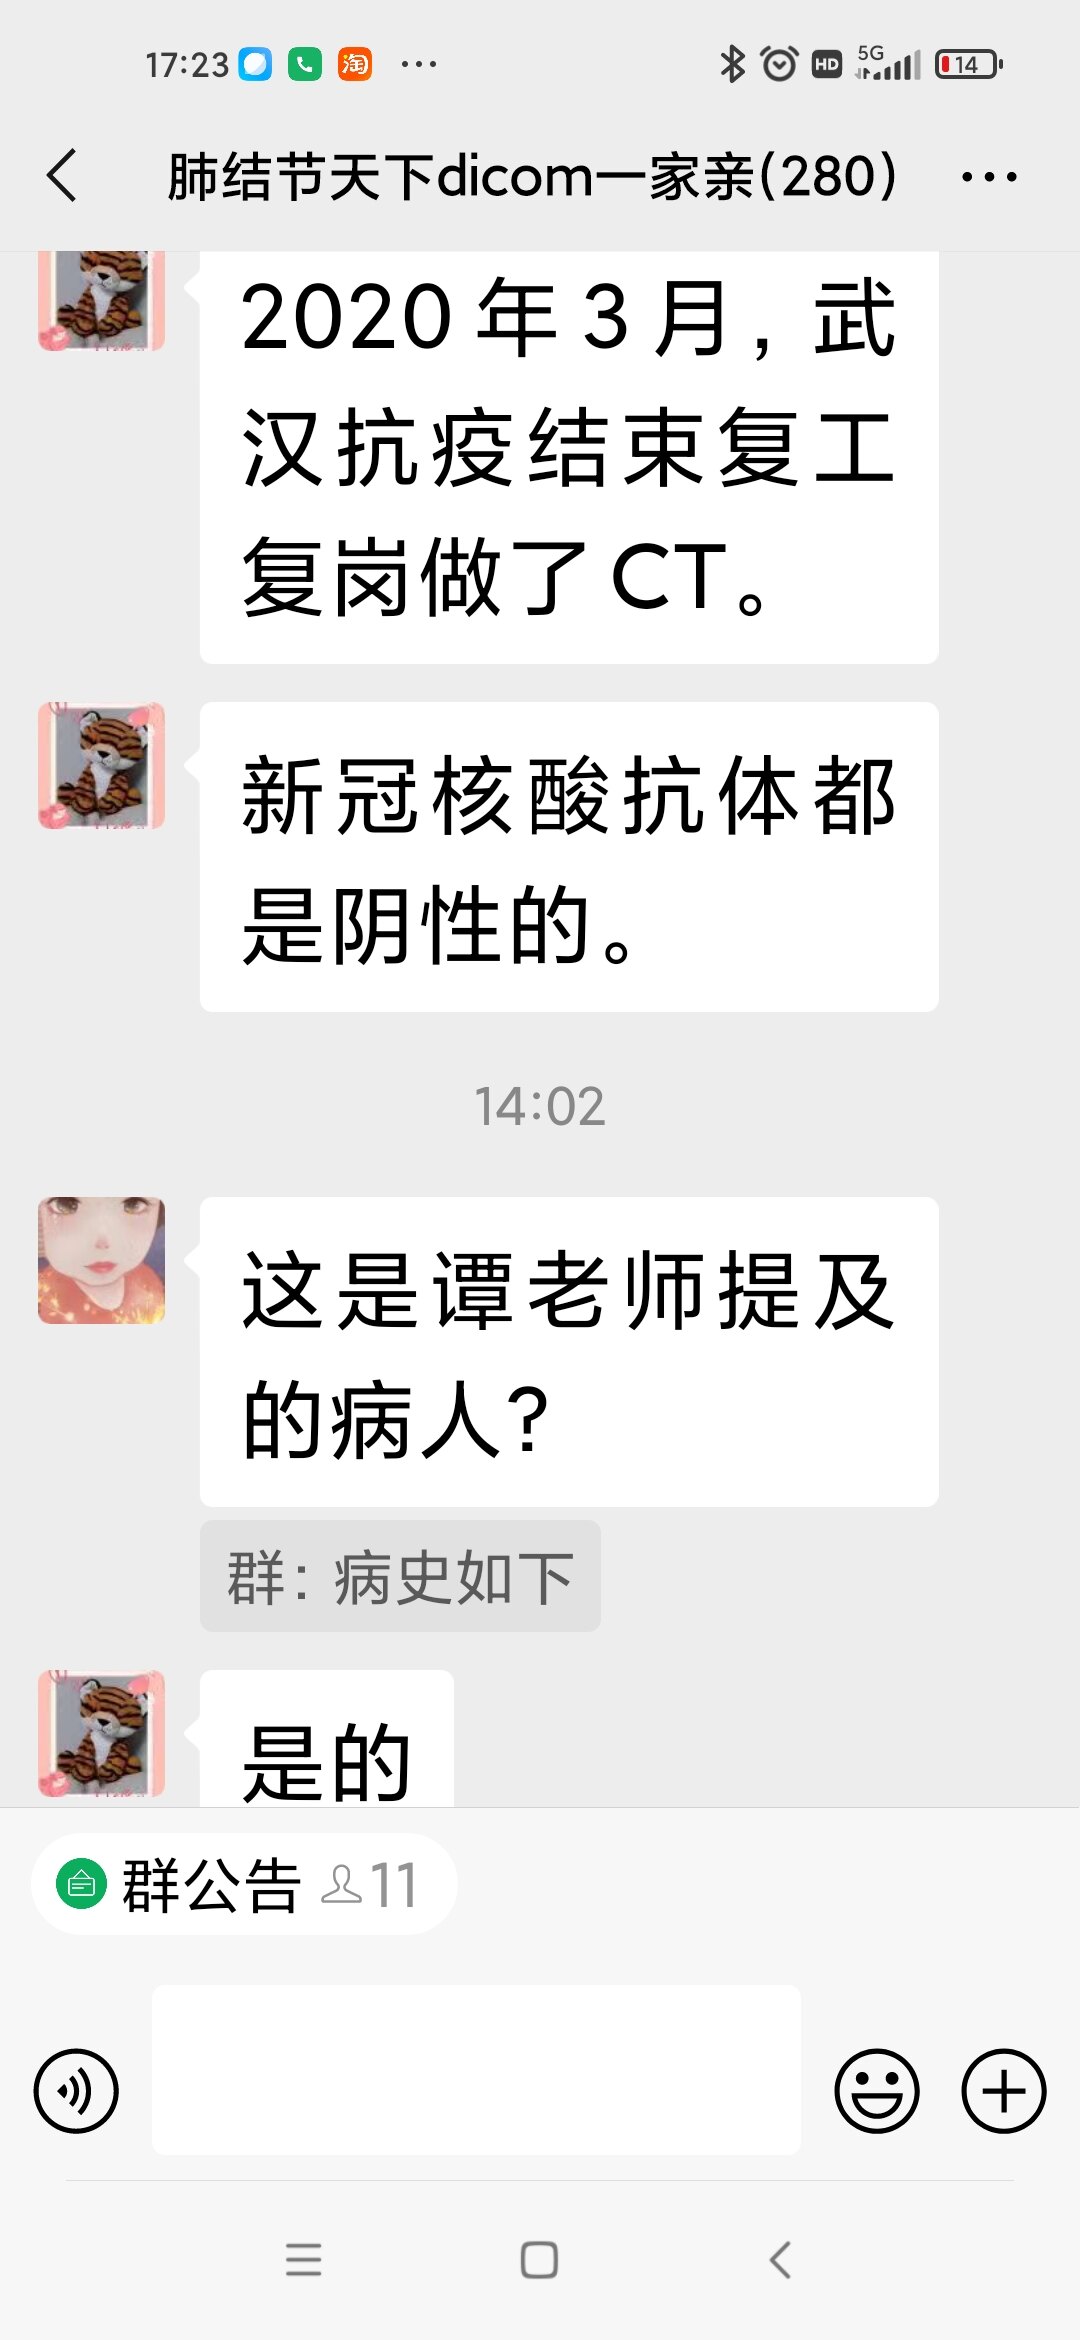

谭先华

副主任医师

武汉市第五医院

放射科

只言片语 之 (7)